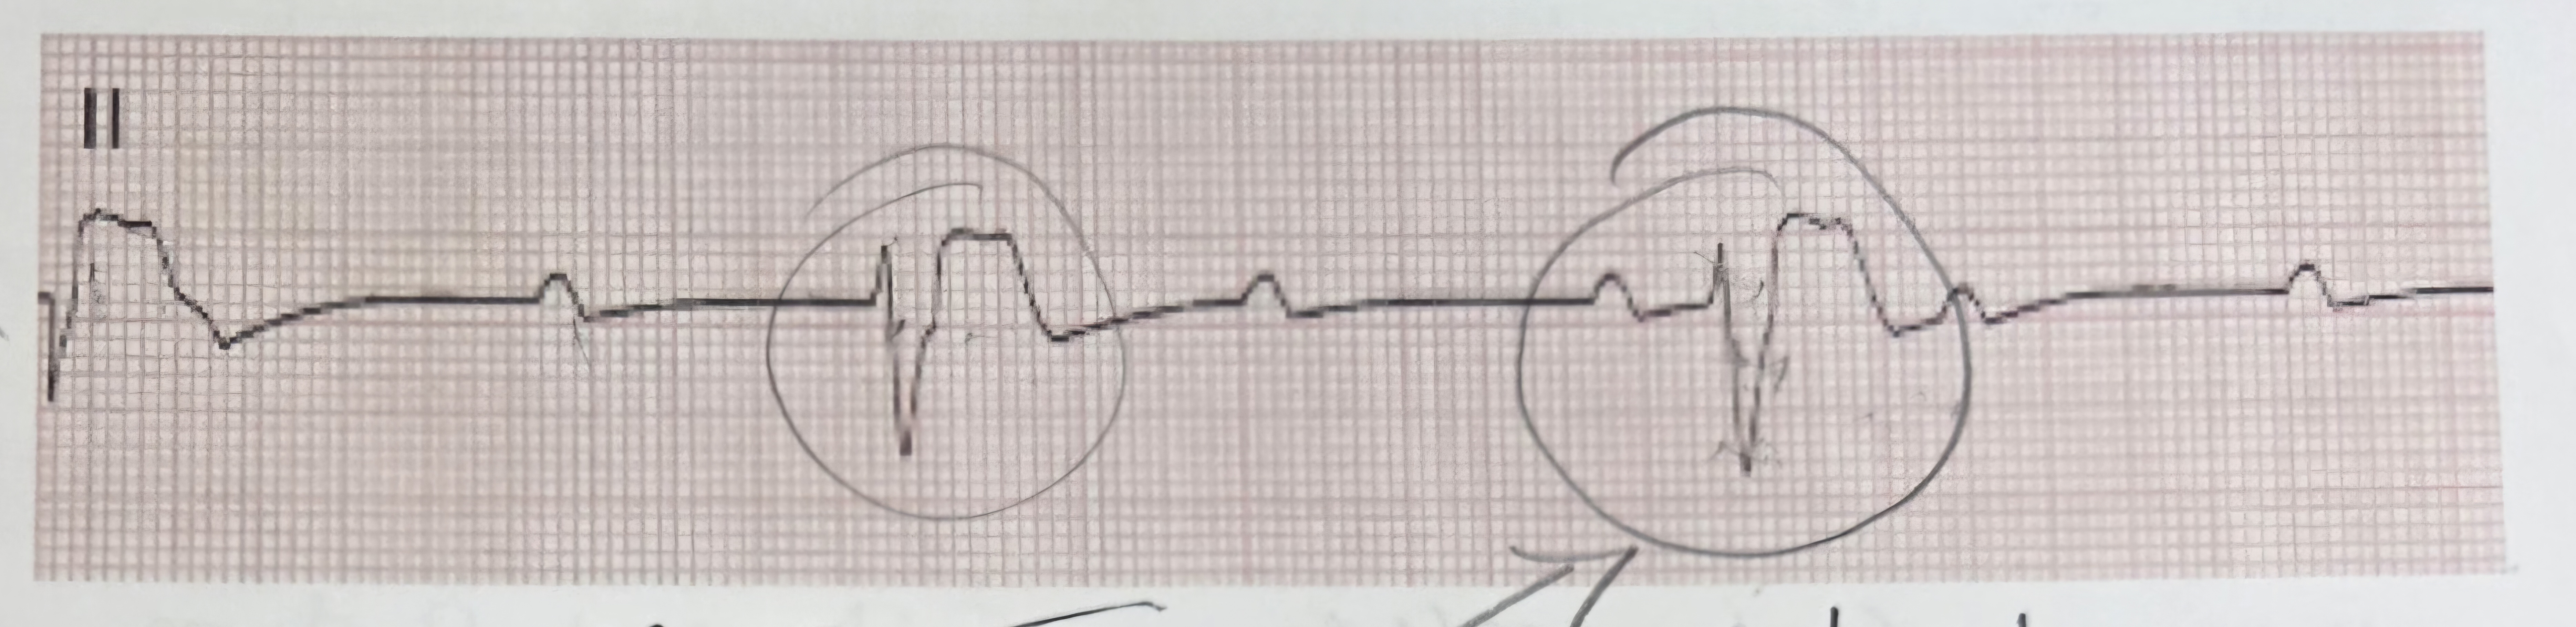

pvc